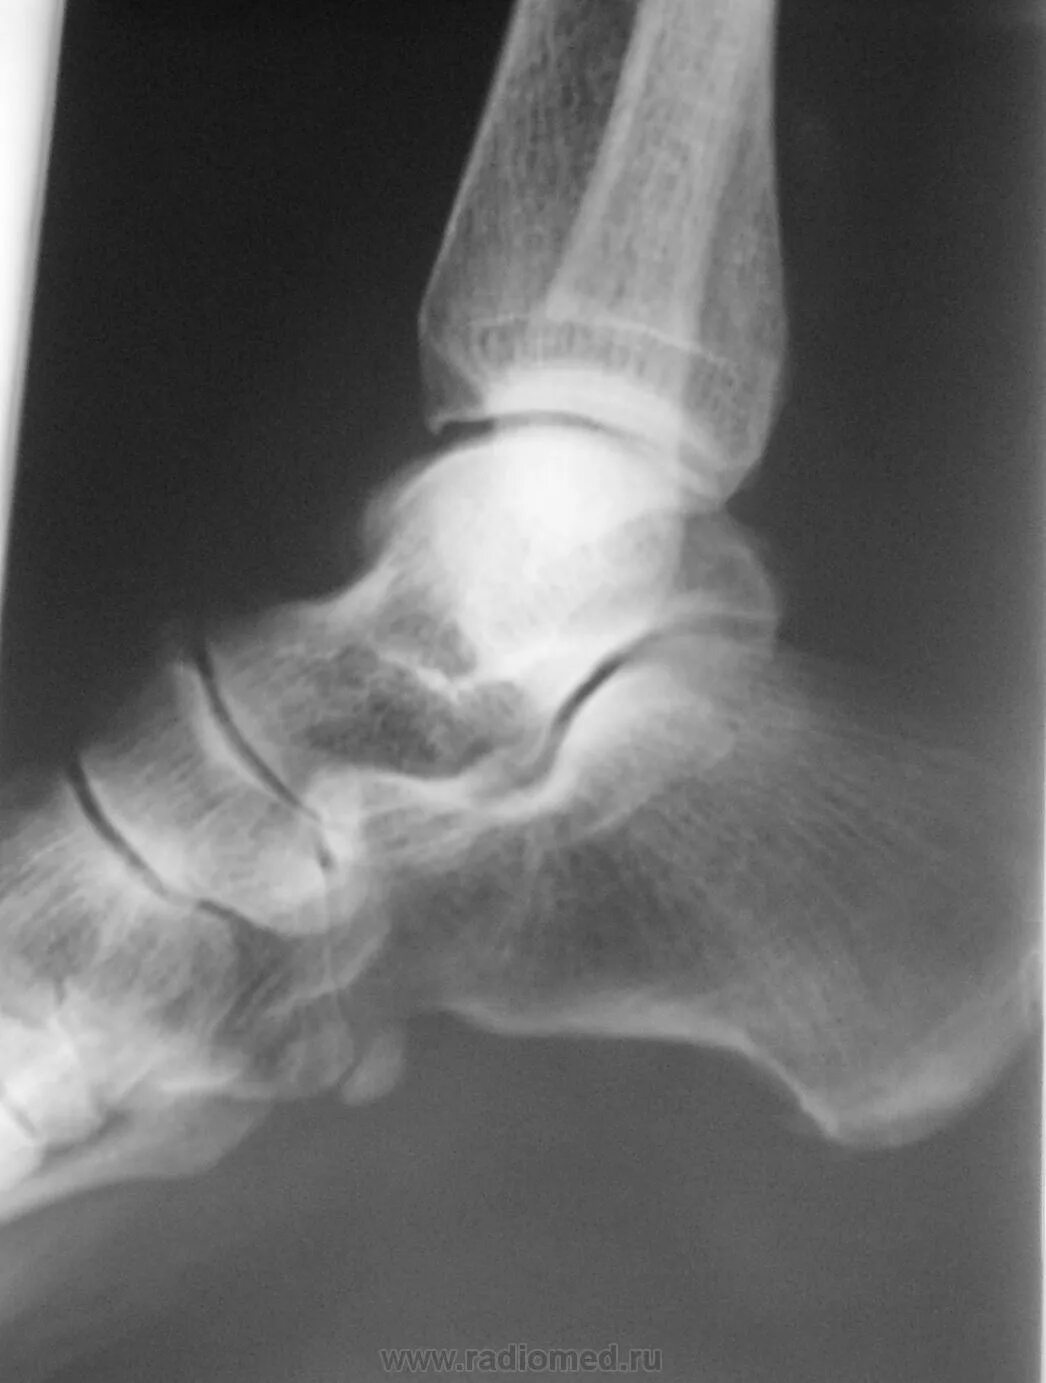

Подвывих сухожилия